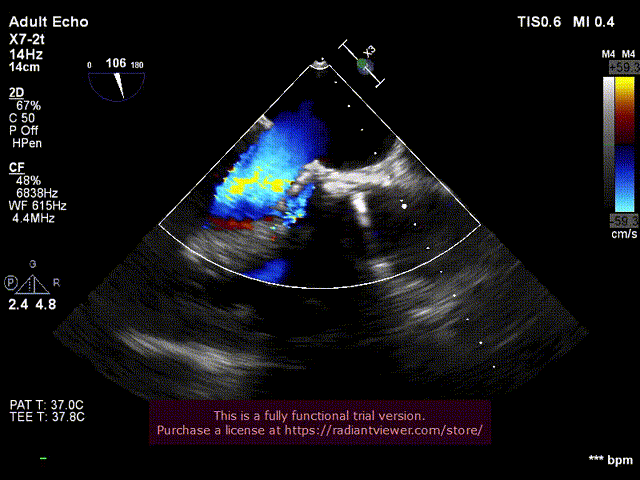

6.经食道超声评估主动脉瓣位SAPIEN 3植入

位置良好,瓣叶运动良好,无反流